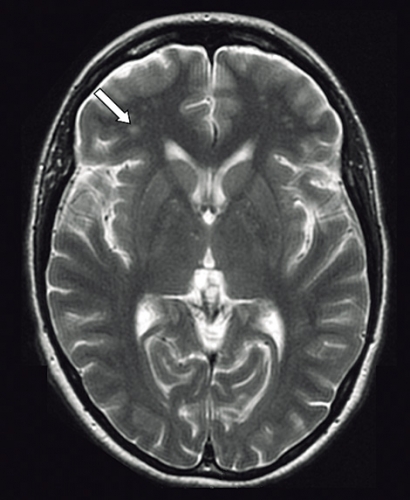

Ny MR-undersökning visade på oförändrad bild med förändringar i vit substans utan säker patologisk signifikans (Figur 1). På den kliniska bilden av limbisk encefalit genomgick patienten DT torax och buk, som inte visade på tumör.